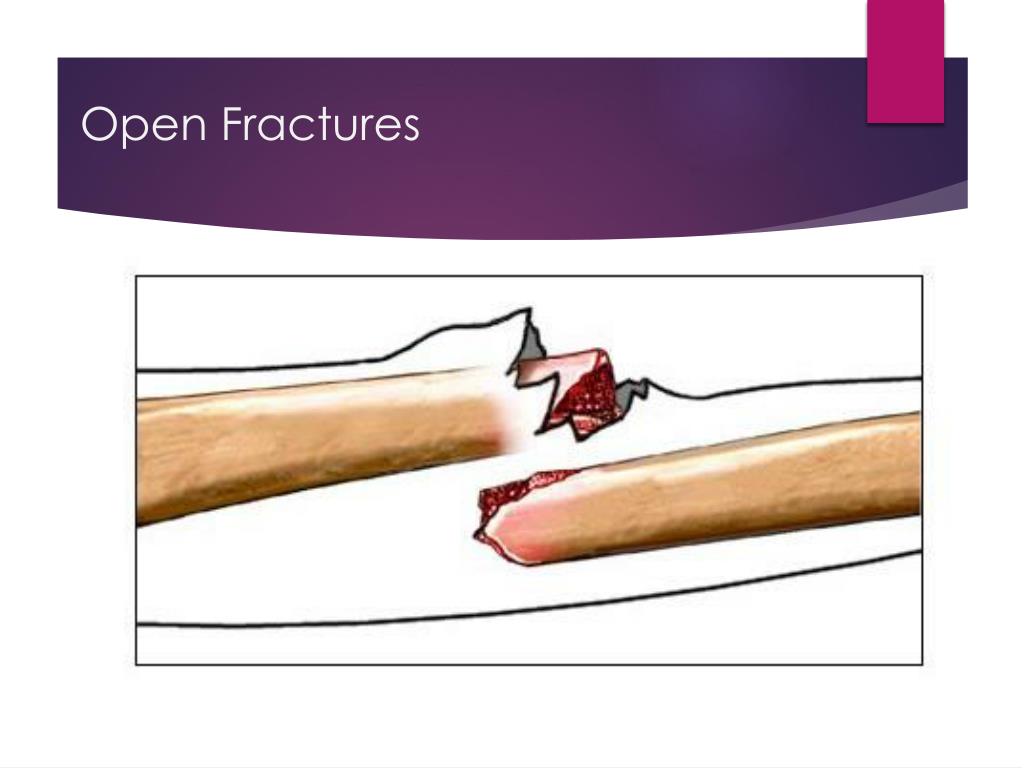

- Definitions. An open fracture, commonly referred to as a compound fracture, is a type of fracture characterized by an open wound on the skin that overlays a broken bone.

An open fracture is an injury where the fractured bone and/or fracture hematoma are exposed to the external environment via a traumatic violation of the soft tissue and skin. The skin wound may lie at a site distant to the fracture and not directly over it. Therefore, any fracture that has a concomitant wound should be considered open until proven otherwise.[1][2]

Open fractures are fractures with direct communication to the external environment. Diagnosis is made clinically by assessing the size and nature of the external wound as well as obtaining radiographs of the bone at the location of the soft tissue injury.

by John Furst · February 3, 2016. An open fracture occurs when a broken bone (fracture) causes a break in the skin. This is a serious injury and requires prompt first aid treatment. The two main risks from open fractures are infection and bleeding. Broken bones are vulnerable to infection, so if they are exposed to the environment there is ...